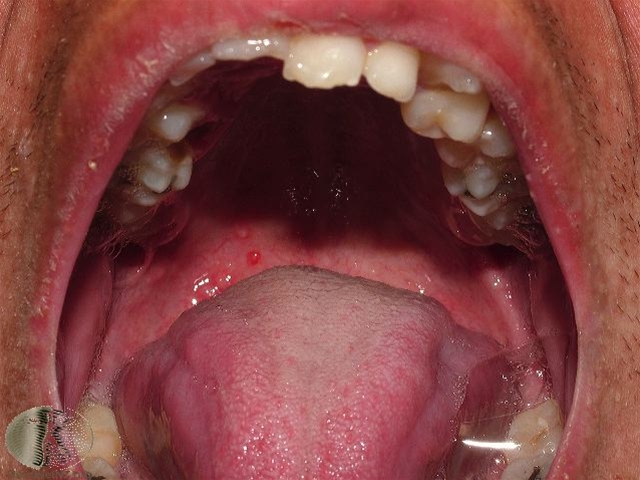

Fotoet viser skoldkopper i mundens slimhinde.

Skoldkopper begynder som en lille rød plet, der efter nogle timer bliver til en lille blære med klart indhold, som endelig brister. Efter et par dage dannes en skorpe, der efterhånden falder af. Udslættet klør meget ofte og varer 4-6 dage, inden alle elementer er skorpebelagt. Tilsvarende kan ses blærer i mundslimhinden.